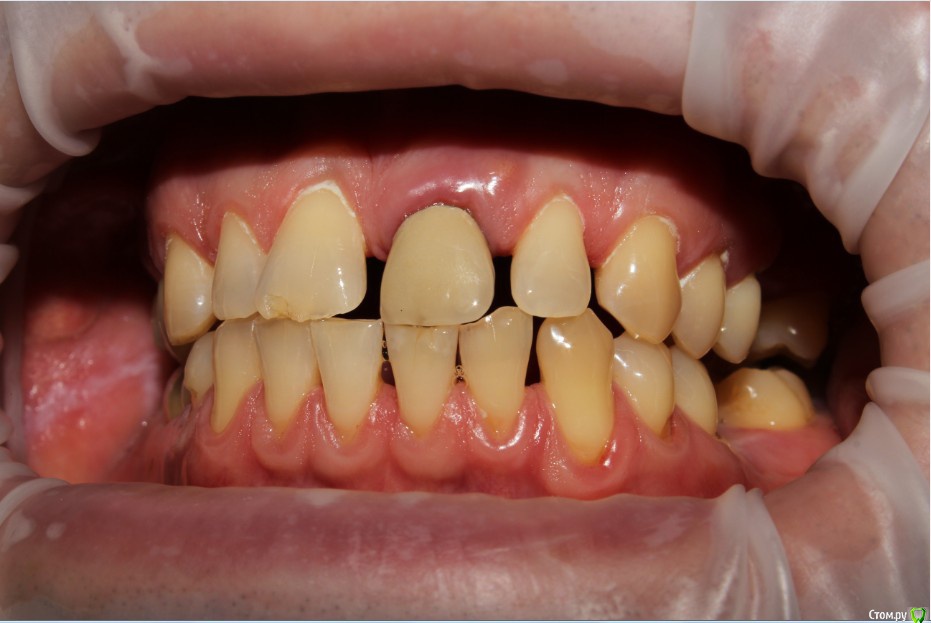

Рустам Опубликовано 20 июля, 2015 Поделиться Опубликовано 20 июля, 2015 Здравствуйте коллеги! Подскажите по клиническому случаю пожалуйста. Обратился пациент в клинику с подвижной коронкой на зубе 2.1, на рентгене диагностирован перелом корня, планируем удаление с одномоментной имплантацией и желательно с немедленной нагрузкой. Система имплантатов "Osstem", на этой системе я ранее не протезировал (работал с "Mis" и "Super Line") и вообще ранее немедленно не нагружал имплантаты. Хирург назначил удаление и иплантацию на 23.07, я смогу принять пациента только 24.07 утром, необходимо заказать временный абатмент, подскажите какой именно из каталога нужно заказать?Имплантолог заказал два имплантата Osstem TSIII SA диаметром 4,0 и 4,5.Я планирую делать временную прямым способом по ключу снятому со старой коронки во рту. Может лучше через оттиск заказать лабораторную временную?P.S. пациента эстетически все устраивало, ортодонтию не хочет. Ссылка на комментарий